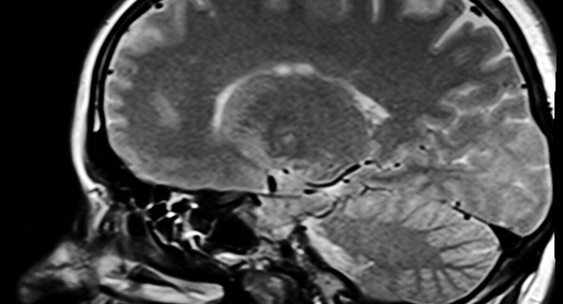

Ученые Нижегородского университета имени Лобачевского запатентовали приложение, которое позволяет оценить биологический возраст и здоровье мозга.Живем в Нижнем

В основе разработки лежит модель машинного обучения Cognitive-Age-V, обученная на данных более 1800 человек в возрасте от 20 до 85 лет.НИА Нижний Новгород

Как подчеркивают ученые, у пациентов с деменцией наблюдается ускоренное старение мозга в среднем на 15,4 года, а у людей с умеренными когнитивными нарушениями — на 7,6 года.Нижегородская Правда